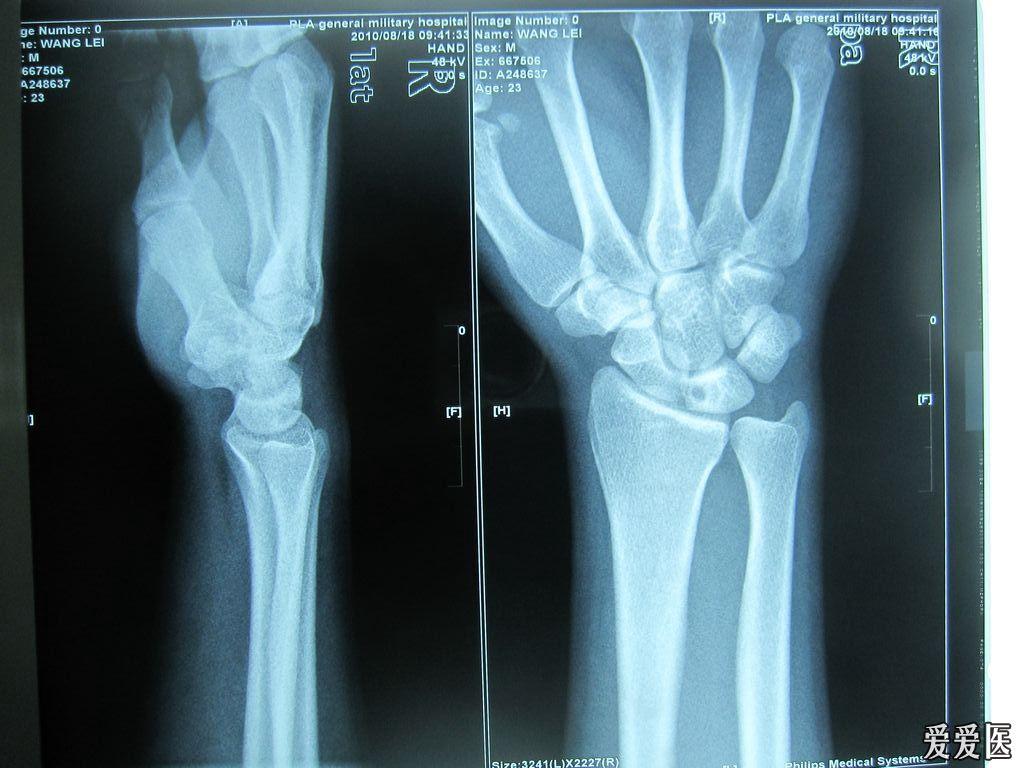

临床上月状骨受伤引起缺血性坏死的经典病例 请各位老师支招

临床上月状骨受伤引起缺血性坏死的经典病例请各位老师支招

关键词 月骨骨折